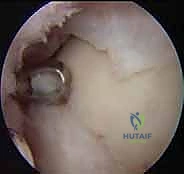

- التنظير التشخيصي للمفصل (Diagnostic Arthroscopy): في بعض الحالات المعقدة، يتم إدخال كاميرا دقيقة (منظار) داخل الكاحل لتقييم الغضروف بالرؤية المباشرة وتقييم مدى صلابته.

1. الاستكشاف والتنظيف: يُدخل الدكتور هطيف الكاميرا الدقيقة لتقييم حجم الآفة بدقة، وتنظيف أي أنسجة تالفة أو أجسام حرة داخل المفصل.

2. أخذ الخزعة (Biopsy): يتم أخذ عينة صغيرة جداً من الغضروف السليم (بحجم حبة العدس أو أقل من 200-300 مليغرام) من منطقة غير حاملة للوزن في المفصل (Non-weight bearing area)، بحيث لا يؤثر أخذها على وظيفة الكاحل.

1. الوصول إلى المفصل: تُجرى هذه العملية عادة كجراحة مفتوحة صغيرة (Mini-open) أو في بعض الأحيان عبر المنظار (حسب موقع الآفة). قد يتطلب الوصول إلى بعض الآفات العميقة إجراء قطع عظمي مؤقت (Osteotomy) في الكعب الإنسي (Malleolus) للوصول للآفة، ثم يتم إعادة تثبيته بمسامير طبية في نهاية العملية.

2. تحضير السرير العظمي: يقوم الدكتور هطيف بإزالة جميع الأنسجة الغضروفية الميتة والعظم المتصلب وصولاً إلى الحواف السليمة والصحية للغضروف والعظم، لإنشاء بيئة دموية مثالية لاستقبال الخلايا.

3. زراعة الغشاء الخلوي: يتم قص الغشاء الكولاجيني المشبع بملايين الخلايا الغضروفية الخاصة بالمريض ليتطابق تماماً مع حجم وشكل الآفة.

4. التثبيت: يُثبت الغشاء في مكانه باستخدام لاصق حيوي طبي (Fibrin Glue) وأحياناً غرز دقيقة جداً قابلة للامتصاص.